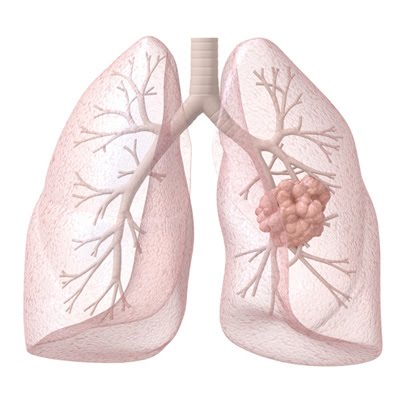

克唑替尼耐受后控制ALK阳性肺癌的药物布加替尼

大约3-5%的肺癌是由ALK基因的变化引起的。2011年,FDA批准加速批准药物克唑替尼,以针对这些ALK变化。然而,仍存在两个主要问题:克唑替尼不会进入大脑,因此无法在中枢神经系统中靶向ALK阳性肺癌,而癌症的遗传多样性使得能够抵抗药物的亚群的后期生长,导致新的增长。作为回应,研究人员一直在积极开发下一代ALK抑制剂。

克唑替尼,以及溴化抑制素和其他下一种ALK抑制剂是一类被称为“激酶抑制剂”的药物的成员,这些药物通过限制其对能量的获取来寻求沉默与各种致癌蛋白相关的信号传导。在这种情况下,所有ALK抑制剂的目标首先是禁止由ALK融合基因异常表达引起的蛋白质信号传导,这是所谓的ALK阳性肺癌的根本原因。与克唑替尼相比,下一代ALK抑制剂对大脑的渗透性更好,并且对ALK中的一系列不同突变起作用,这些突变作为对克唑替尼的抗性机制而出现。然而,它们可能并非全部以相同的程度穿透大脑,并且它们可能并非都在相同范围的抗性突变上发挥作用。